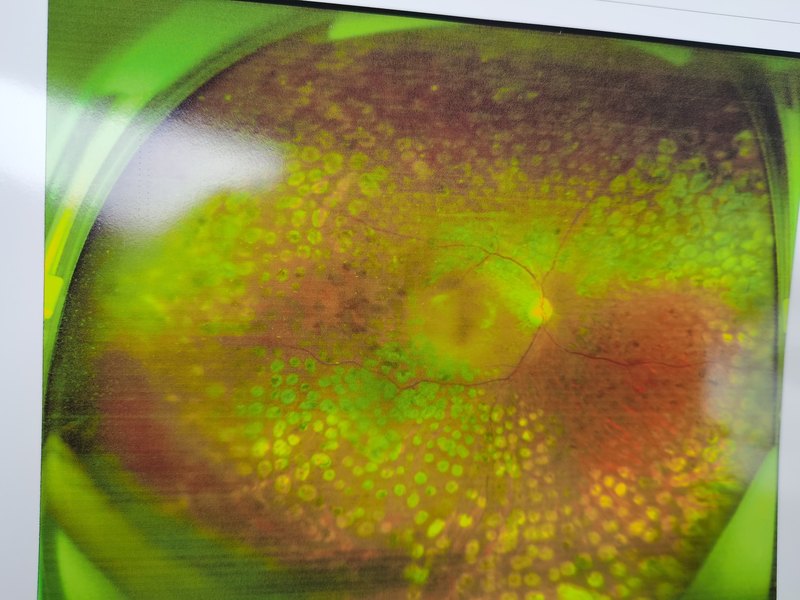

糖尿病眼底病,選擇哪種激光?

內(nèi)分泌系統(tǒng)疾病影響全身,會(huì)引起眼部多種病變和不適。例如,高血糖可以引發(fā)糖尿病性視網(wǎng)膜病變、糖尿病性白內(nèi)障、糖尿病性角膜病變、干眼癥等一系列眼病,這是因?yàn)楦哐且鹑砺匝装Y和氧化應(yīng)激狀態(tài)會(huì)累及結(jié)膜、角膜、晶狀體、視網(wǎng)膜、脈絡(luò)膜等眼球各層結(jié)構(gòu)。糖尿病性白內(nèi)障是糖尿病常見的眼部并發(fā)癥,屬于代謝性白內(nèi)障的一種,常常雙眼發(fā)病,原先透明的相機(jī)鏡頭就因?yàn)槔锩妗疤嵌嗔恕本妥兂闪四:溺R頭,有時(shí)晶狀體甚至?xí)?到2個(gè)月內(nèi)就完全混濁。糖尿病患者在眼科檢查中發(fā)現(xiàn)患有白內(nèi)障的比例相當(dāng)高。那么,眼底病變和白內(nèi)障醫(yī)生究竟先治療哪個(gè)?治療規(guī)范主要是首先全面評(píng)估內(nèi)分泌系統(tǒng)疾病引起的各種眼部病變,依照疾病的輕重緩急和對(duì)視力的影響程度予以相應(yīng)處置和治療,最大程度保護(hù)患者視功能。目前先進(jìn)的眼部檢查手段可以對(duì)眼球從前到后做一個(gè)詳細(xì)的結(jié)構(gòu)和功能檢查。舉例來說,有的患者就診時(shí)同時(shí)患有糖尿病性視網(wǎng)膜病變合并糖尿病性白內(nèi)障,眼底看到大量出血點(diǎn),治療上最緊迫的是盡快完成視網(wǎng)膜激光光凝來穩(wěn)定眼底出血的情況,防止眼底出血進(jìn)一步加重,進(jìn)展為玻璃體腔大出血導(dǎo)致短時(shí)間內(nèi)失明;在視網(wǎng)膜激光光凝完成,眼底病情得到穩(wěn)定,再擇期進(jìn)行白內(nèi)障手術(shù)進(jìn)一步提高視覺質(zhì)量。而有的患者來眼科就診時(shí)白內(nèi)障程度已相當(dāng)嚴(yán)重,眼底完全觀察不清,這時(shí)候就需要首先進(jìn)行白內(nèi)障手術(shù)恢復(fù)屈光介質(zhì),爭(zhēng)取檢查眼底和治療的機(jī)會(huì),在白內(nèi)障手術(shù)完成后及早進(jìn)行散瞳眼底檢查,根據(jù)病變具體情況進(jìn)行眼底病的治療。因此,糖尿病患者眼底疾病和白內(nèi)障的治療兩者是相輔相成的。(上海市第一人民醫(yī)院眼科沈胤忱)

糖尿病視網(wǎng)膜病變,出現(xiàn)棉絨斑代表什么?

糖尿病視網(wǎng)膜病變的病人,什么情況下不建議打激光?

糖尿病視網(wǎng)膜病變

四分鐘帶你了解“糖尿病視網(wǎng)膜病變”!

糖尿病眼病

糖尿病視網(wǎng)膜病變?cè)撛趺崔k?

最近我接診到不少糖尿病視網(wǎng)膜病變的患者,大家都有不少疑問,但是不同階段的患者有不同的憂慮和疑問,關(guān)注的點(diǎn)可能不太一樣。在這里我想給大家解答一下。問:我才體檢出糖尿病視網(wǎng)膜病變,視力還湊合,還需要進(jìn)一步檢查治療嗎?答:糖尿病視網(wǎng)膜病變是糖尿病的常見并發(fā)癥。查出眼底病變應(yīng)該立即找眼底病醫(yī)生進(jìn)一步檢查評(píng)估,明確病變嚴(yán)重程度,規(guī)范治療或者觀察。錯(cuò)過治療時(shí)機(jī)或者諱疾忌醫(yī)可能意味著后續(xù)視力嚴(yán)重受損的可能,而且治療難度越來越大。儲(chǔ)大夫見過很多因?yàn)殄e(cuò)過最佳治療時(shí)機(jī)導(dǎo)致病情加重,結(jié)局比較差的患者。特別是年輕患者,血糖控制不佳的患者,往往病變進(jìn)展很快。問:我糖尿病視網(wǎng)膜病變,出血,已經(jīng)看不見,病情很嚴(yán)重了,還能治療嗎?都想放棄治療了答:嚴(yán)重的糖尿病視網(wǎng)膜病變?nèi)匀挥袡C(jī)會(huì)獲得良好的治療效果,晚期的病例,即使維持0.05的視力對(duì)患者的生活也有巨大的幫助。問:我的糖尿病黃斑水腫已經(jīng)眼內(nèi)注射藥物很多次了,反反復(fù)復(fù),已經(jīng)沒有信心了,該怎么辦?答:目前糖尿病黃斑水腫的治療主要依靠眼內(nèi)注射藥物,輔助激光,口服藥物。疾病的特點(diǎn)就是反反復(fù)復(fù),需要做的就是堅(jiān)持治療,規(guī)范治療,配合醫(yī)生,大多會(huì)有較好的視力預(yù)后。問:我的糖尿病視網(wǎng)膜病變需要做哪些治療?能提高視力嗎?答:總體上糖尿病視網(wǎng)膜病變的治療是一個(gè)系統(tǒng)工程,核心治療手段是上面提到的眼內(nèi)注藥,激光,手術(shù),基礎(chǔ)治療是控制血糖血壓等。治療的目的是穩(wěn)定病情,維持或提高視力,減少各種并發(fā)癥的風(fēng)險(xiǎn)。一部分患者的視網(wǎng)膜結(jié)構(gòu)受到了明顯的破壞,那么視力提升就不會(huì)很明顯,治療會(huì)穩(wěn)定視力,但是不治療只會(huì)越來越差。問:醫(yī)生說我的糖尿病視網(wǎng)膜病變需要做手術(shù)了,手術(shù)風(fēng)險(xiǎn)大嗎?答:目前微創(chuàng)玻璃體切除已經(jīng)廣泛應(yīng)用于增殖性糖尿病視網(wǎng)膜病變,創(chuàng)傷小,效果良好。常規(guī)的手術(shù)一個(gè)小時(shí)以內(nèi),復(fù)雜的兩小時(shí)左右。手術(shù)前以及手術(shù)中及術(shù)后需要輔助眼內(nèi)注射藥物,減少手術(shù)并發(fā)癥,幫助術(shù)后恢復(fù)。除了復(fù)雜病例,大多不用填充硅油,患者不用害怕術(shù)后要趴什么的。儲(chǔ)大夫做過不少糖尿病視網(wǎng)膜病變患者,不少術(shù)后第一天都有0.5以上的視力。